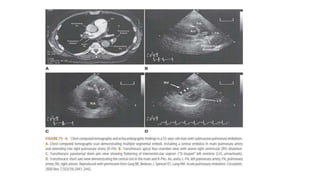

ECHOCARDIOGRAPHY

• Acute PE may lead to RV pressure overload and dysfunction, which can be detected by

• Disturbed RV ejection pattern (so-called ‘60–60 sign’) or on depressed contractility of the RV

free wall compared with the RV apex (‘McConnell sign’)

• Echocardiographic examination is not recommended as part of the diagnostic work-up in

haemodynamically stable, normotensive patients with suspected (not high-risk) PE

• This is in contrast to suspected high-risk PE, in which the absence of echocardiographic signs

of RV overload or dysfunction practically excludes PE as the cause of haemodynamic

instability

• Mobile right heart thrombi are detected by transthoracic or transoesophageal

echocardiography (or by CT angiography)